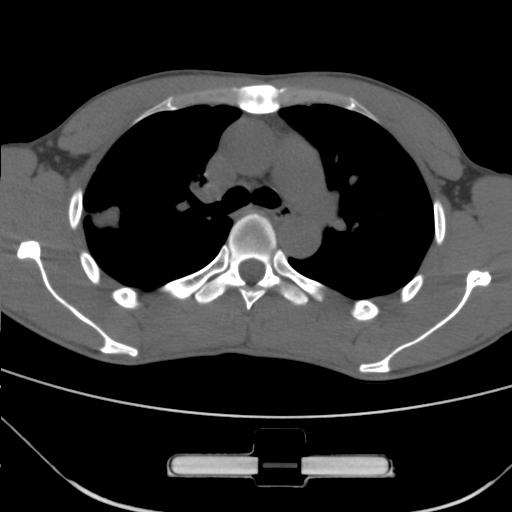

标题: CT25483:肺部病变 请指教

车祸伤者

右肺上叶后段近胸膜下结节样异常密度灶,似见分页及毛刺,考虑右肺上叶周围型肺ca,建议穿刺病理检查

缺乏病史,症状体征,但这个孤立结节具备了几乎所有的恶性征象:分叶,毛刺,空泡征,胸膜凹陷征,血管集束。